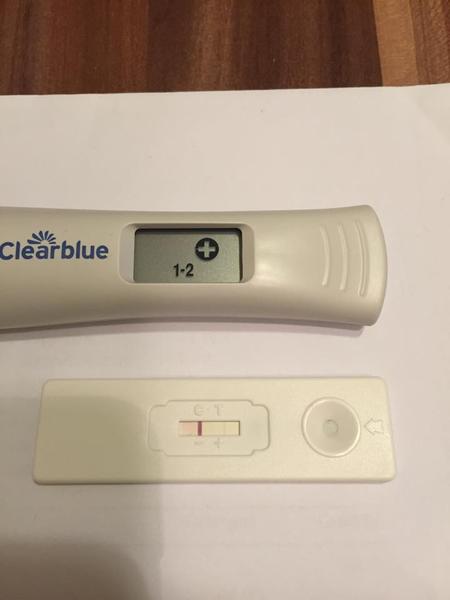

Chcela by som sa s vami podelit o moje testiky, v pondelok som davala foto mojho ´´dušíka´´ ktorý už vtedy nebol duchom, postupne silneli takto...avšak včera rano som sa zobudila na obrovsku bolest podbruska zbehla som na gyndu, kde hcg 115 na sone este nic, ale na lavom vajecniku utvar velkosti 4cm, mozne mimonaternicove tehitenstvo? s 3ma prizmurenymi ocami ma pustili domov s tym,ze v sobotu musim prist na dlasie hcg,ktore ak bude viac ako dvojnasobok sme v suchu...predpokladam ze ten utvar bola iba cysta a tie boli z jej prasknutia...teraz som uz fajn 🙂 a dnes som si spravila pre istotu dalsi test, a on silnie, takze myslim ze to MMT mozme vylucit 🙂 len pekne pozitivne! ale viac uvidime zajtra.